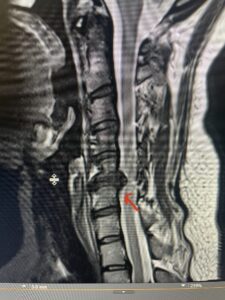

Fig 2a Sagittal and axial T2 weighted cervical MRIs demonstrating large C4 5 herniated disc with spinal cord compression red arrows

This 47-year-old male who four months prior was lifting weights developed sharp pain in his neck. After that he developed progressive numbness in his arms, neck pain and headache. He said that the right arm was worse than the left. On examination the patient had long tract weakness on the right side which included his triceps, finger extensors, hip flexors, and dorsiflexors. The patient did not have hyperreflexia. MRI (Fig. 2) demonstrated a massive, extruded disc herniation with severe cord compression. The patient because of progressive myelopathy and spinal cord compression was indicated for anterior cervical discectomy and fusion at C4-5 (Fig. 3). Patient had significant improvement of weakness and numbness post operatively.

Fig. 2a Sagittal T2-weighted cervical MRI demonstrating large C4-5 herniated disc with spinal cord compression (red arrow)